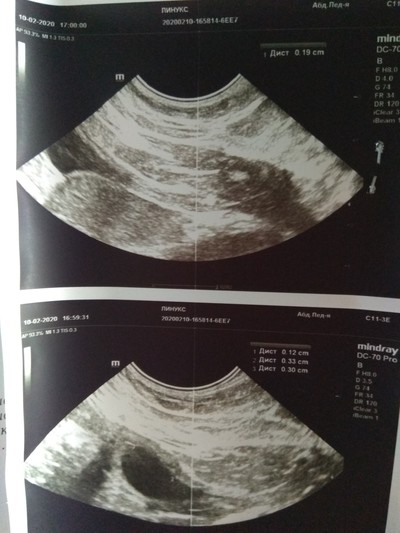

Вот как-то так выглядит кот напросвет. Теплоты там особо не видно, зато есть целый комплект косточек и перелом четвертой пястной кости.

Пока люди отвернулись, Линукс порвал сетку, вышел погулять на карниз и превратился в ракету класса "окно-асфальт". Жив, цел, орёл, месяц ходил со спицей в лапе, и всё равно умудрялся буянить по ночам.